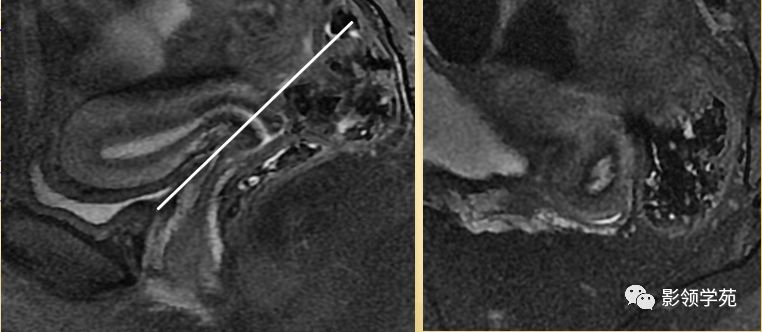

宫颈

T1WI表现为较均匀一致的稍低信号

高分辨率T2WI可看到4层结构

最内层-高信号粘液

粘膜层(柱状上皮)-高信号,低于粘液信号

纤维间质(结合带)-低信号

肌层-中等信号

阴道壁

阴道粘膜 为复层鳞 状上皮

T1WI 呈中等稍低信号

T2WI内带:高信号(上皮、粘液)

外带 :低信号